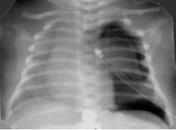

Снижение пневматизации легких, воздушные бронхограммы, границы сердца на рентгенограмме ещё различимы (Рис.5).

Рисунок 5. РДС. Рентгенограмма в прямой проекции, в горизонтальном положении. Верхние доли легких и средняя доля справа неоднородно слабоинтенсивно затемнены, корни легких расширены, не структурны. Сосудисто-интерстициальный рисунок легких деформирован, усилен, размыт. Тень средостения с нечётким контуром, протекционно смещена влево за счёт подворота. ( Диагностика и лечение РДС недоношенных // метод. рекомендация, 2007)